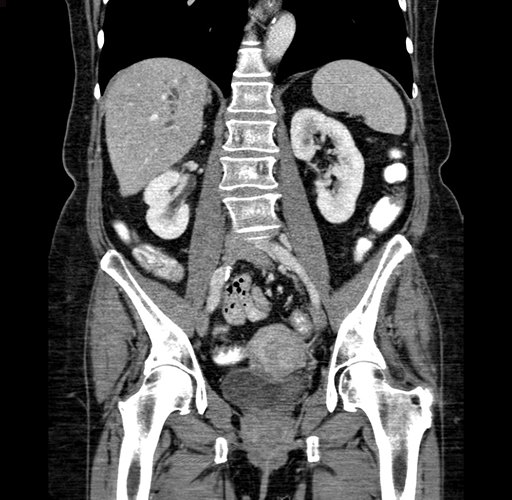

Pre-Chemo: Coronal Venous

Coronal Venous